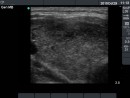

First examination (first row):

Clinical presentation: A 29-year-old woman was referred for evaluation of complaints suggesting hyperthyroidism. She had no eye signs.

Palpation: Both lobes were enlarged. No nodule was palpable.

Ultrasonography: Both lobes were enlarged, moderately hypoechogenic, inhomogeneous and displayed increased vascularization.

Diagnosis: Graves' hyperthyroidism.